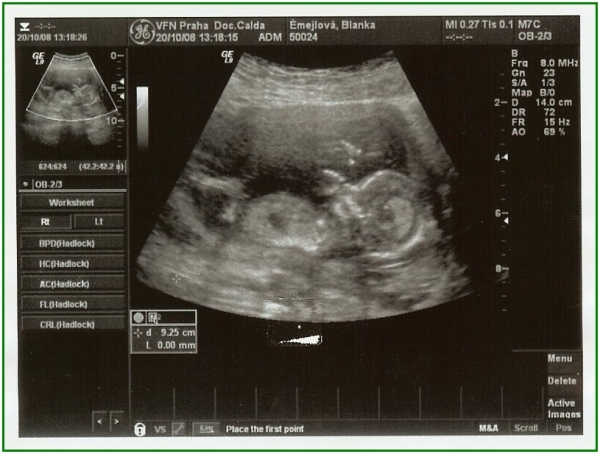

Pod pokličkou podruhé